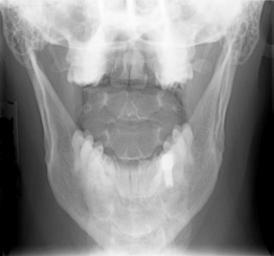

MAKE A MEME View Large Image Cervical Xray AP View.jpg en X-ray of cervical spine neck AP front view with mouth open to show C1-C2 This series of x-rays were part of pre-surgical evaluation to help identify spinal instability Patient is a 37 year old male with a ...

Keywords: Cervical Xray AP View.jpg en X-ray of cervical spine neck AP front view with mouth open to show C1-C2 This series of x-rays were part of pre-surgical evaluation to help identify spinal instability Patient is a 37 year old male with a history of multiple neck traumas with pain and muscle spasms and dental implant in lower jaw Excerpt from radiologist's report FINDINGS Five views of the cervical spine including flexion and extension were performed There is no evidence of fracture bone destruction or malalignment There are degenerative bone and is changes at C5-6 There is no evidence of cervical instability on the flexion and extension views The facet joints are well aligned Bony spurring is narrowing the C5-6 neural foramina bilaterally IMPRESSION Degenerative changes at C5-6 No evidence of instability Ragioagraphie aux raysons X du rachis cervical cou AP vue avant avec la bouche ouverte pour voir C1-C2 Cette série de radiographies faisaient partie de l'évaluation pré-chirurgicale pour aider à identifier une instabilité vertébrale Le patient est un homme de 37 ans ayant des antécédents de traumatismes multiples cou avec des spasmes et des douleurs musculaires et implant dentaire à la mâchoire inférieure Extrait du rapport du radiologiste RÉSULTATS Cinq vues de la partie cervicale de la colonne vertébrale ont été faites dont en flexion et en extension Il n'y a pas de signe de fracture de destruction osseuse ni de défaut d'alignement On observe un phénomène de gégénérescence osseuse des changements en C5-6 Il n'existe aucune preuve de l'instabilité du cou sur les radios montrant la flexion et l'extension Les facettes articulaires sont bien alignés Bony spurring is narrowing the C5-6 neural foramina bilaterally IMPRESSION Changements dégénératifs eu C5-6 Aucune preuve d'instabilité own medical image work for hire Stillwaterising 2010-04 File Cervical Xray Extension jpg File Cervical Xray Extension view jpg File Cervical Xray Lateral View jpg Magnification 0 4x converted from lossy DICOM file Cc-zero X-rays of the neck Mouths open